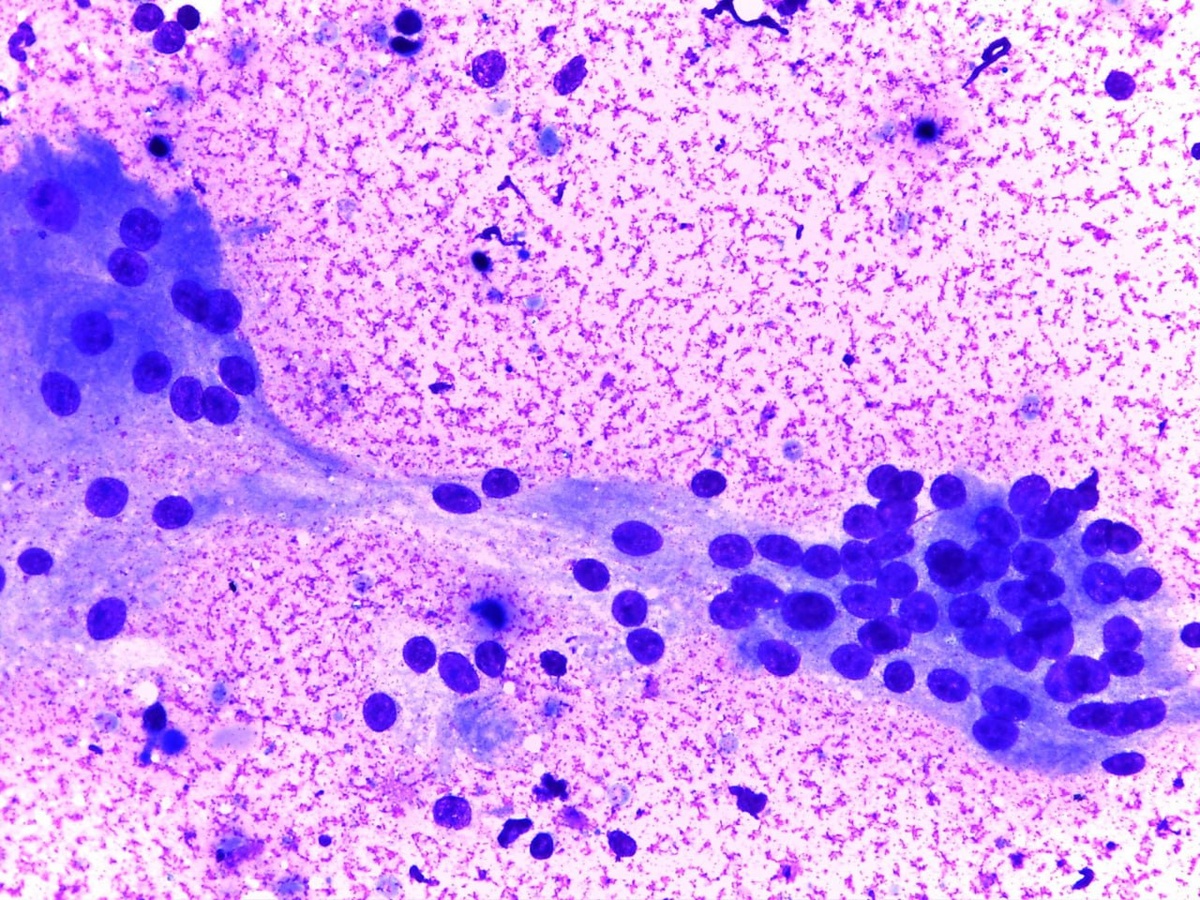

Гигантские клетки (полинуклеарные макрофаги) при гранулематозном тиреоидите (подострый тиреоидит\тиреоидит Де Кервена). Материал ТАБ. #щитовиднаяжелеза #цитология #назаметку

Гигантские клетки (полинуклеарные макрофаги) при гранулематозном тиреоидите (подострый тиреоидит\тиреоидит Де Кервена). Материал ТАБ.